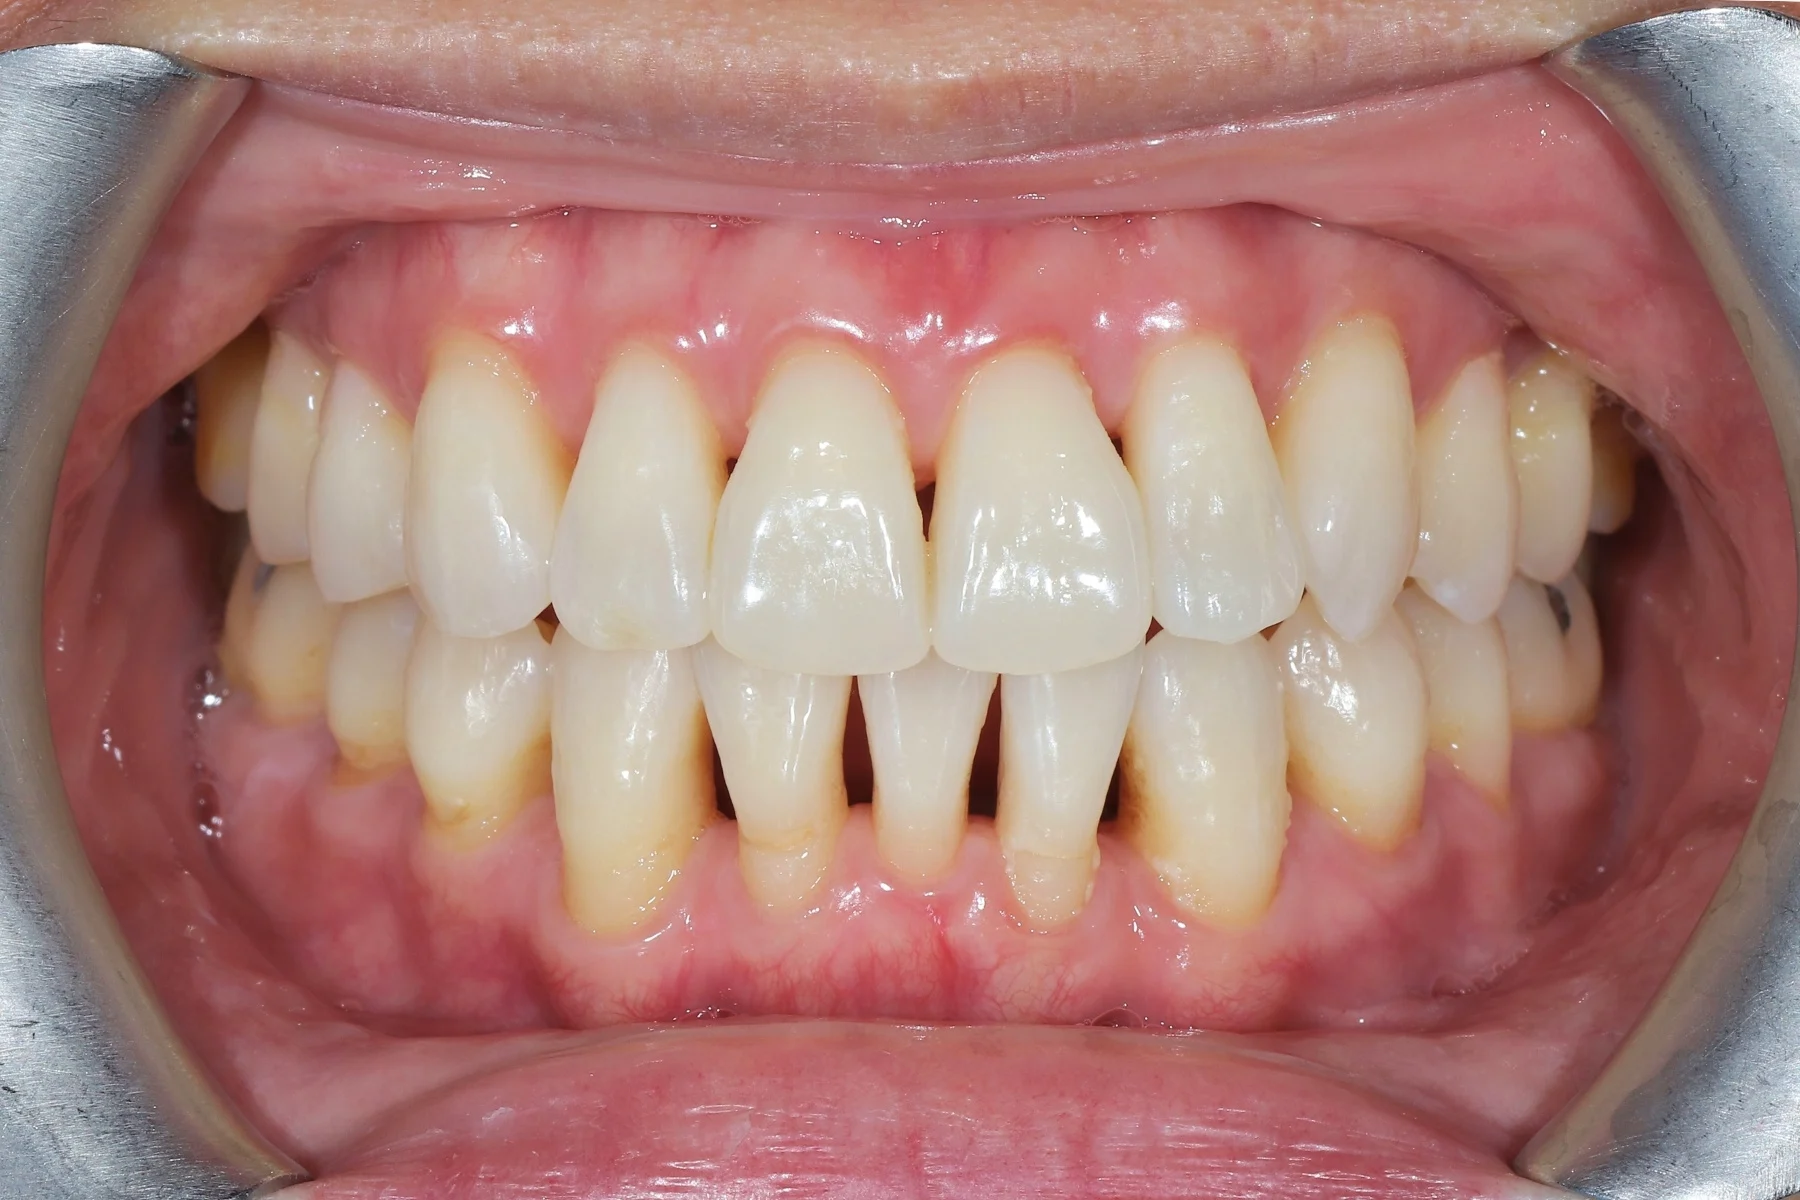

Dentist 陳昕 全口照護醫師 看診項目 前牙美學仿生樹脂補牙/全科牙醫 學經歷 臺北醫學大學牙醫系學士 前天主教新店耕莘醫院醫師 前臺北榮民總醫院醫師 亞洲齒列再生研究學會Advance植牙補綴專科訓練 微光私塾牙周雷射微創治療技術訓練 臺灣牙醫顯微美學治療學會會員醫師 中華審美牙醫學會會員醫師 CASE 案例分享 滲透型樹脂修復 主治醫師 陳昕 治療時間 單次療程 主訴 想處理前牙白白的色斑 前牙美學/仿生美學樹脂 主治醫師 陳昕 治療時間 單次療程 主訴 牙齒整齊,但門牙中間縫隙明顯,影響笑容美觀 前牙美學/陶瓷貼片 主治醫師 陳昕 治療時間 約1個月 主訴 兩顆門牙缺角,想要重建外觀 前牙美學/滲透型樹脂修復 主治醫師 陳昕 治療時間 單次療程 主訴 門牙有長期存在的白斑與表面不平整,影響外觀與自信 前牙美學/仿生美學樹脂 主治醫師 陳昕 治療時間 約兩週 主訴 矯正後的黑三角縫問題 前牙美學/仿生美學樹脂 主治醫師 陳昕 治療時間 約三週 主訴 因牙周病產生的黑三角縫 前牙美學/牙冠增長術、仿生全瓷牙冠 主治醫師 陳昕 治療時間 約6個月 主訴 牙齒排列不整、假牙外觀不自然 前牙美學/仿生美學樹脂 主治醫師 陳昕 治療時間 約兩週 主訴 露齒笑時黑三角縫明顯,覺得不好看 前牙美學/仿生美學樹脂+噴砂美白 主治醫師 陳昕 治療時間 約兩週 主訴 露齒笑時有不好看的黑三角縫,容易有茶垢沉澱,讓縫隙更明顯 牙齒美白/噴砂美白+冷光美白 主治醫師 陳昕 治療時間 單次療程 主訴 前牙泛黃且染色明顯,影響外觀與自信 牙齒美白/噴砂美白 主治醫師 陳昕 治療時間 單次療程 主訴 牙齒表面有喝咖啡、抽菸造成的外部染色,影響外觀與自信 點此載入更多 Column 精選文章 FEATURED 精選案例 【牙科修復案例】陶瓷貼片可以做一顆嗎?單顆門牙缺角修復,陶瓷貼片重建自然笑容 2026-01-16 從「假笑」到「自然笑容」的轉變——認識「牙冠增長術」與「仿生全瓷冠」 2025-10-14 Video 精選影音